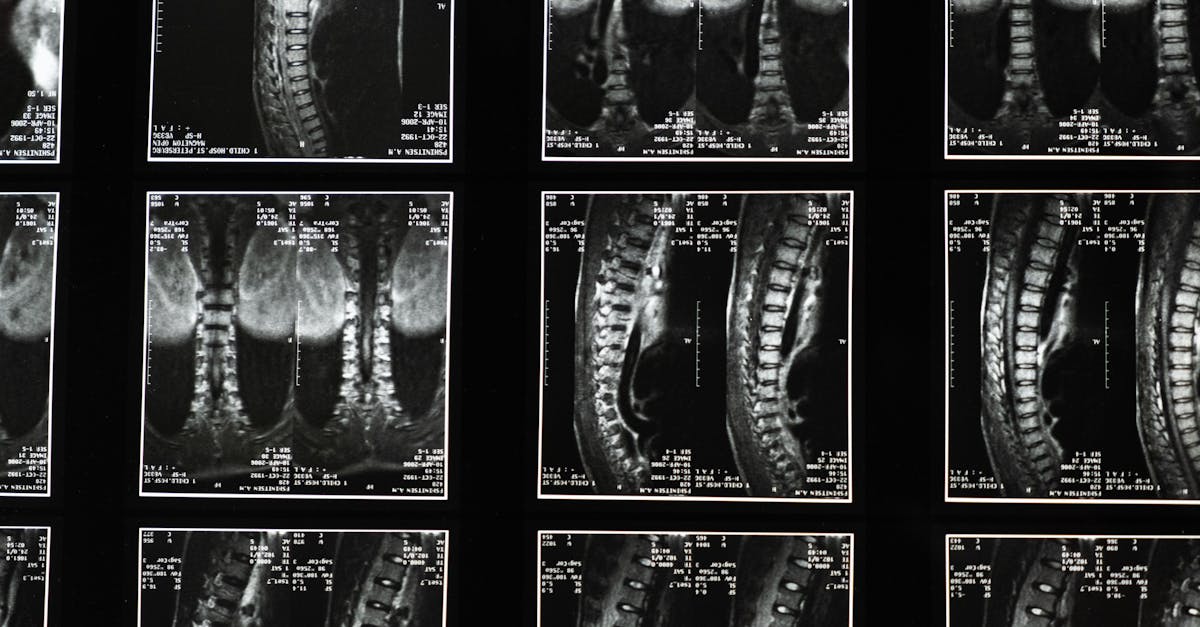

La décompression neurovertébrale est une approche innovante et non invasive qui cible spécifiquement les troubles de la colonne vertébrale, en particulier les maux de dos chroniques. Cette technique a pris de l’importance au cours des dernières décennies comme un traitement efficace pour soulager les douleurs liées à des conditions telles que les hernies discales et les discopathies. En appliquant des méthodes de traction contrôlées, la décompression neurovertébrale allège la pression sur les disques intervertébraux et les nerfs, offrant ainsi aux patients un répit par rapport à leurs douleurs persistantes.

Le processus de décompression neurovertébrale repose sur des principes scientifiques qui se fondent sur l’anatomie de la colonne vertébrale et son fonctionnement. En créant un espace entre les vertèbres grâce à des techniques de traction, cette méthode favorise la réhydratation des disques intervertébraux, permettant aux disques de retrouver leur forme et leur fonctionnalité normales. Cela entraîne une réduction de l’inflammation et de la douleur, et encourage une guérison naturelle des structures affectées par le temps et l’usure.